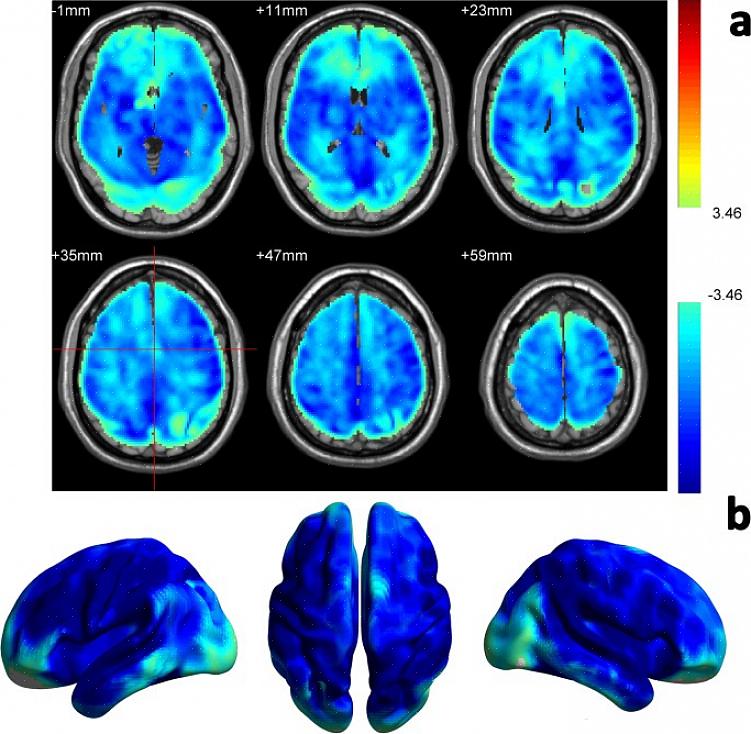

ד"ר ליאן שמידט ועמיתיה פרסמו מאמר בכתב העת bioRxiv בנוגע לניסוי שערכו. בניסוי שתתה קבוצת מתנדבים משקאות אנרגיה וקבוצה נוספת שתתה משקה קל רגיל. למרות שאיש לא ידע מה הם שותים, כולם חשבו שהם משקאות אנרגיה. לאחר מכן, החוקרים בדקו אותם כדי להעריך את הביצועים הקוגניטיביים שלהם. בהשוואה לבדיקה קודמת שערכו, כולם השתפרו. במילים אחרות, היה אפקט פלצבו ברור.